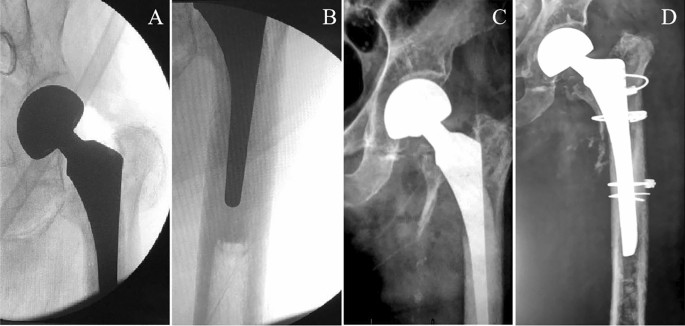

Two treatment methods were adopted. Longer stem revision and internal fixation (LSRIF) with cables was applied in 24 cases (Figs. 1 and 2). Open reduction and internal fixation (ORIF) with cables was done in four cases (Fig. 3). The choice of surgical treatment was based on the patient’s physical condition. The standard treatment was LSRIF, while ORIF was chosen if the patient was in poor condition and could not tolerate LSRIF.

Postoperative pseudo ALT fractures were seen in 28 patients (7 males [25% and 21 females [75%]). The age of the patients at surgery was 73.7 (range: 52–92) years. Of the cases, 27 (96.43%) occurred with non-cemented stems, and 1 (3.57%) with cemented stems (Fig. 4). The basic patient data are summarised in Table 1.

Case 1, an 82-year-old man underwent left hemi-arthroplasty with a cemented stem because of a left femoral neck fracture. (A–B) Two intraoperative radiographs taken with a C-arm machine. (C) After a fall, the continuity of the left medial femoral cortex was interrupted on an anterior–posterior radiograph. (D) Postoperative anterior–posterior radiograph after longer stem revision and internal fixation with cables.

In our series, 27 patients with non-cemented stems (96.43%) sustained a PPFF. The mechanism was as described above. One fracture involved a cemented stem (3.57%); this patient had osteoporosis and it might have been an occult fracture that was not found intraoperatively.